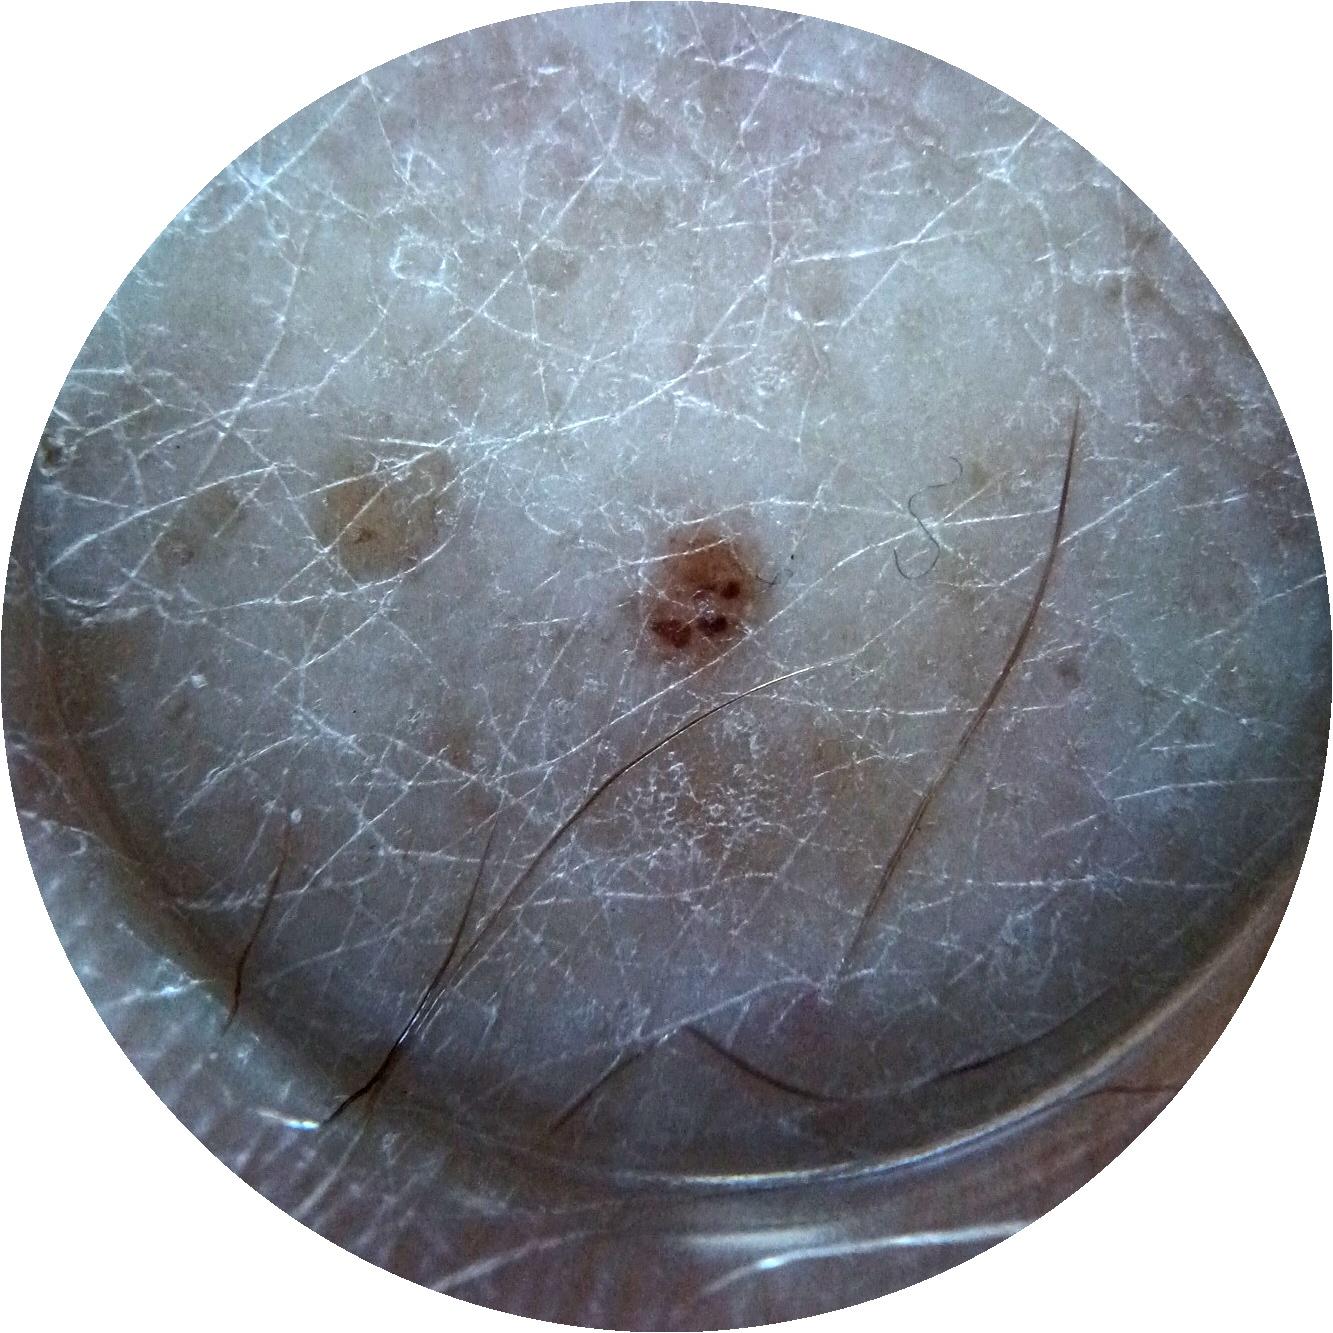

ISIC_7740426

1172 x 1172

Clinical

Field Value

acquisition_day 278

age_approx 65

anatom_site_1 Head and neck

anatom_site_general head/neck

diagnosis_1 Benign

family_hx_mm False

image_manipulation instrument only

image_type dermoscopic

lesion_id IL_9049639

patient_id IP_3152710

personal_hx_mm True

sex male